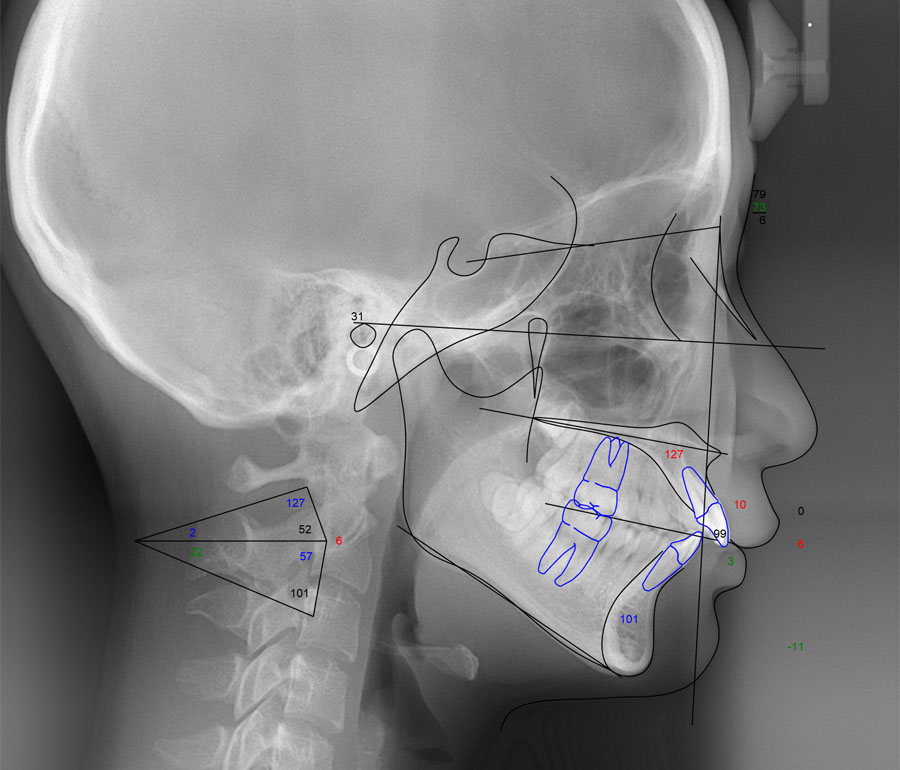

セファロ分析

頭部X線規格写真

治療シミュレーション

採得したデジタルデータをコンピュータ解析します(セファロ分析および治療シミュレーション)。 またマウント模型では、咬み合わせ(咬合)の問題および上下顎骨の前後的および垂直的バランスを評価して治療方針を決定します。 サリバテストでは、口腔内の細菌と唾液の性質を評価し、現在の口腔内環境に合わせた虫歯予防プランを作成します。 検査結果を元に十分な相談の上、できる限り希望に沿えるよう適切な治療の計画を立てます。